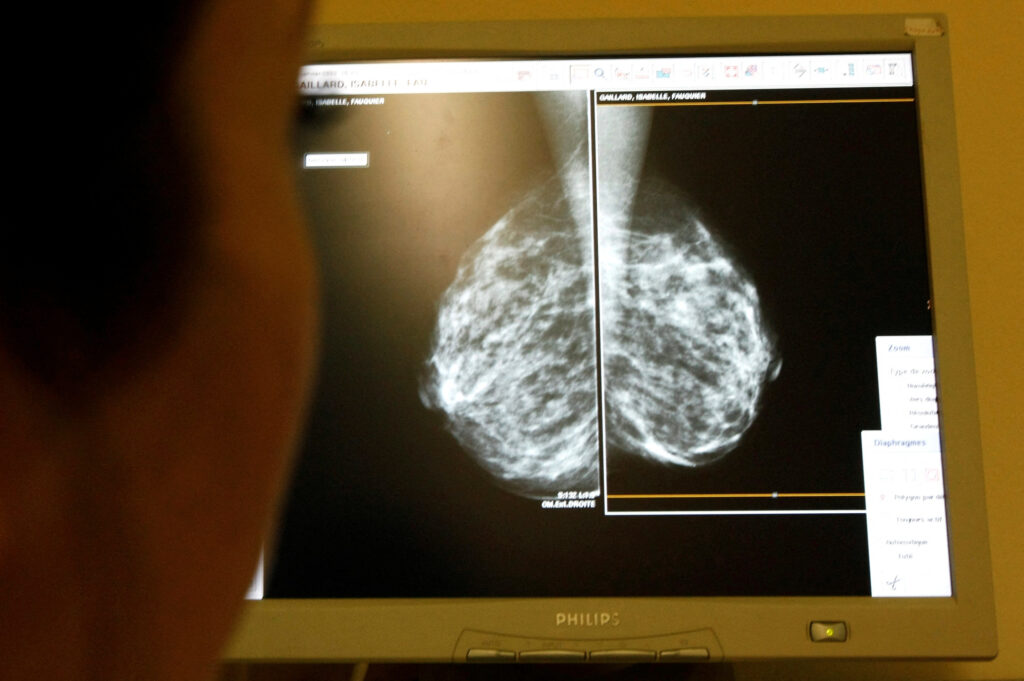

- Mammograms are the gold standard for breast cancer screening. Women are advised to start getting a mammogram at age 40 and annually thereafter. Women with a known family history of breast cancer or a known genetic predisposition should have a conversation with their primary care provider to see if earlier testing is recommended. If there is a family history, it is usually recommended to start screening 10 years before the age at which the first-degree relative was diagnosed for breast cancer.

Mammography and other diagnostic care for breast cancer screening and treatment are available across the island. For those who may benefit from additional specialised options, facilities like Baptist Health Miami Cancer Institute offer advanced diagnostic tools such as digital mammography and 3D imaging that can detect cancers too small to feel. Women with a family history or suspected genetic risk can also access testing for inherited mutations like BRCA1, BRCA2, and PALB2, which can help inform prevention and treatment choices.